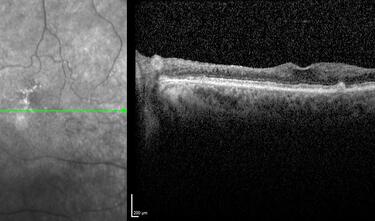

Clase 1 - Conceptos esenciales en fisiología y anatomía de la retina

Clase 15 - Depósitos y signos específicos en DMAE no neovascular

Clase 18 - Signos estructurales diferenciales entre neurodegeneración y exudación en DMAE

Clase 20 - Signos clave en patología traccional vítrorretiniana